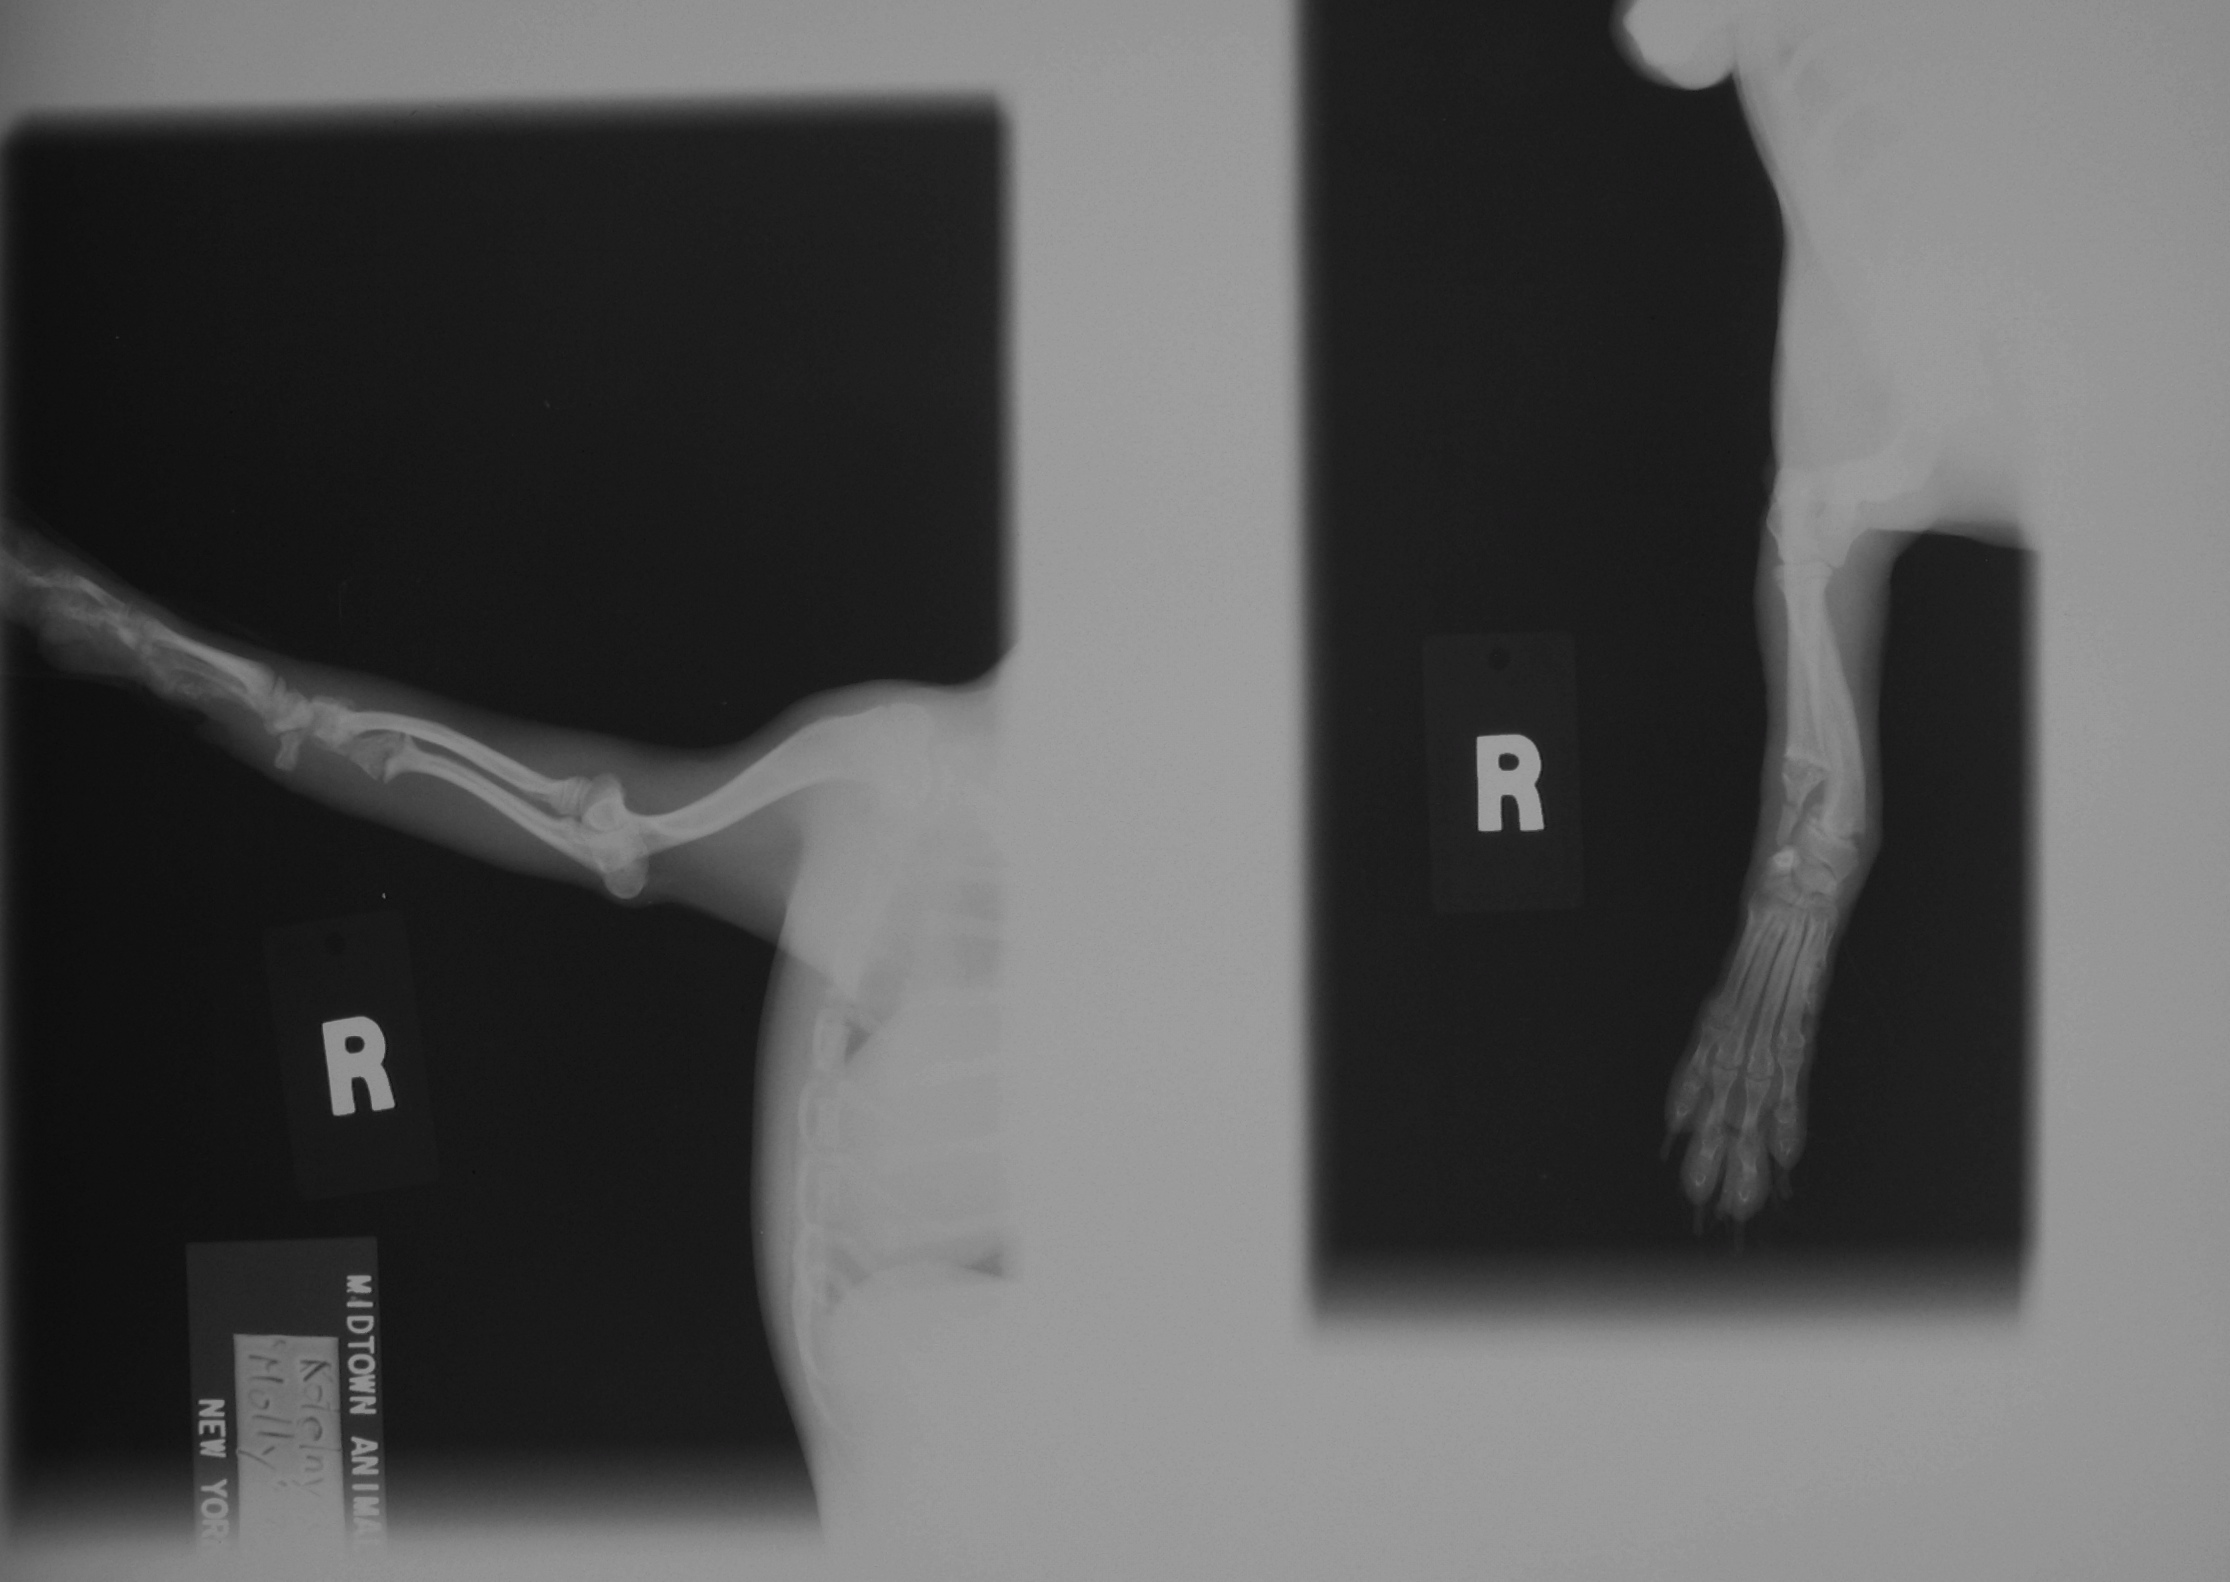

У моей собаки сломана нога! есть рентген лапы! если кто понимает в этом, я бы очень хотела знать насколько серьезен ее перелом? нужна ли ей операция? если нужна, но нет возможности ее сделать, к каким последствиям это может привести?

Мдаа.... судя по снимку перелом давний, долго думаете....

Единственный способ лечения перелома эт оперативно, все остальное издевательство над животным, за что есть соответствующая статья.

Последствия?

Животное - инвалид!